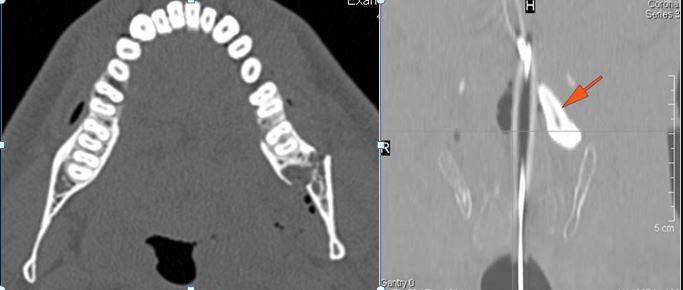

There is bony injury or displacement of the body, angle, ramus, parasymphyseal region, alveolar ridge, and condylar and coronoid process of the mandible. [In case of fracture, describe complexity and displacement].

There are dental fractures and/or missing or displaced teeth.